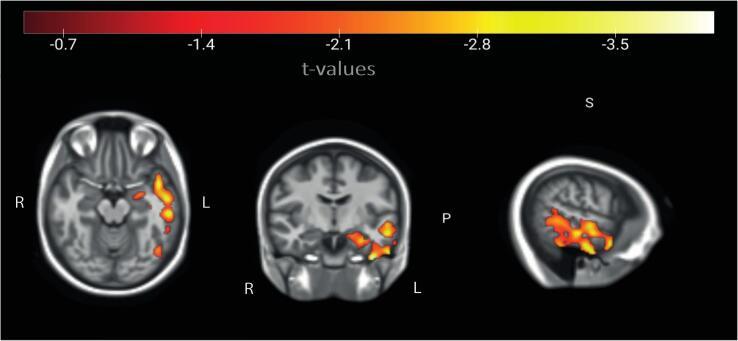

RESULTS

We found increased normalized TSC in the AD cohort compared to elderly control subjects both on global as well as on a region-of-interest-based level. We further confirmed a significant association of local brain volume as well as age with TSC. TSC increase in the left temporal lobe was further associated with the cognitive state, evaluated via the Montreal cognitive assessment (MoCA) screening test. An increase of normalized TSC depending on disease stage reflected by the Clinical Dementia Rating (CDR) was found in our AD patients in temporal lobe regions. In comparison to classical brain volume and cortical thickness assessments, normalized TSC had a higher discriminative power between controls and prodromal AD patients in several regions of the temporal lobe.

我们发现 AD 队列的标准化 TSC 高于老年对照组,无论是在全局还是在基于感兴趣区域的水平上。我们进一步证实了局部脑容量和年龄与 TSC 的显著相关性。左颞叶的 TSC 增加与认知状态进一步相关,通过蒙特利尔认知评估(MoCA)筛选测试进行评估。我们发现,在我们的 AD 患者中,根据临床痴呆评定量表(CDR)反映的疾病阶段,标准化 TSC 会随着时间的推移而增加。与经典的脑容量和皮质厚度评估相比,在颞叶的几个区域,标准化 TSC 在对照组和前驱期 AD 患者之间具有更高的区分能力。

讨论

我们证实了 3T 时 Na-MRI 的可行性,并报告了 AD 患者大脑中多个区域 TSC 的增加,特别是在颞叶区域。此外,为了减少因生理因素(如昼夜节律和实验条件)引起的个体间变异性,我们引入了标准化 TSC 图谱。与经典的 TSC 分析相比,这显示了在不同临床组之间更高的区分能力。总之,Na-MRI 是一种潜在的转化成像标志物,即使在临床可用的场强(如 3T)下,也可用于 AD 的诊断和干预效果的评估。需要进一步阐明 Na-MRI 与其他代谢成像标志物的关联。